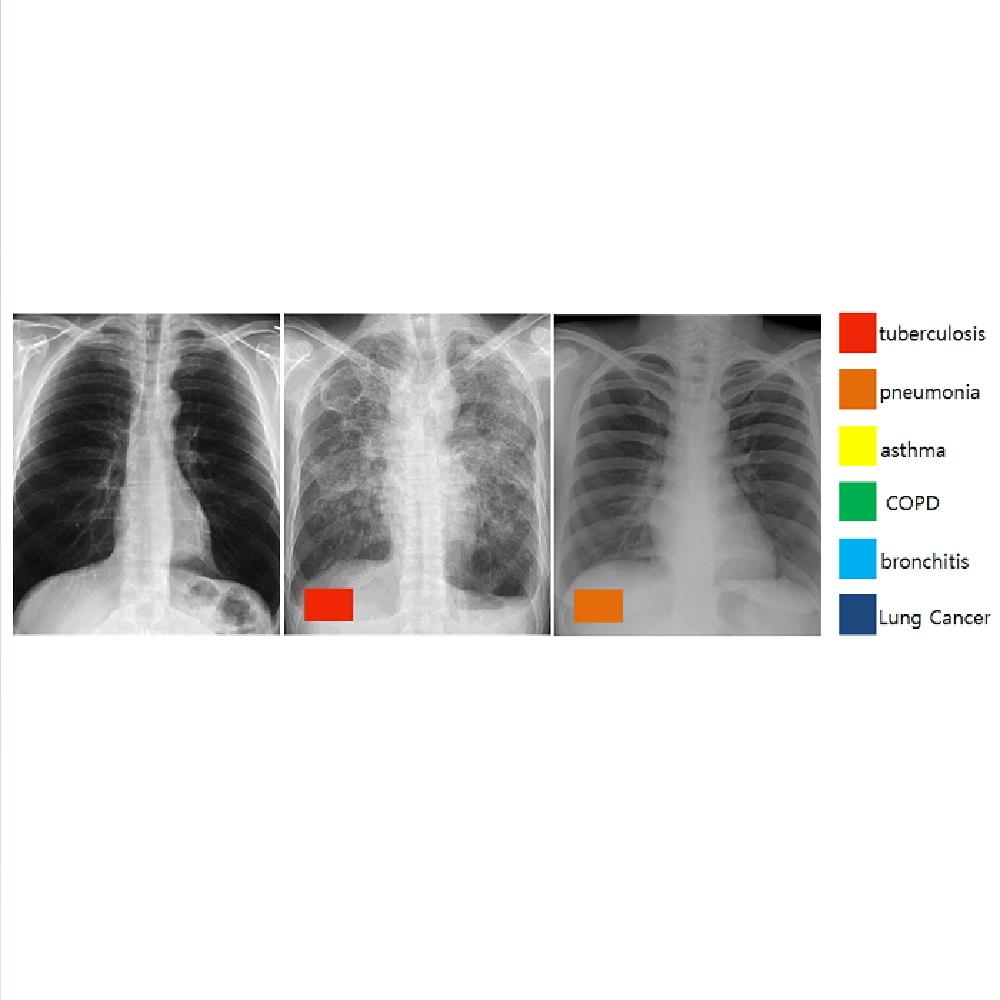

Digital X-ray Radiography Auto decipher

-Based on AI, automagical diagnosis model development for error of DXR-

Need for exact examination of tuberculous (Chest X-Ray)

For tuberculous, the early diagnosis is key

-Need for exact diagnosis of tuberculous, especially where there is no Radionologist